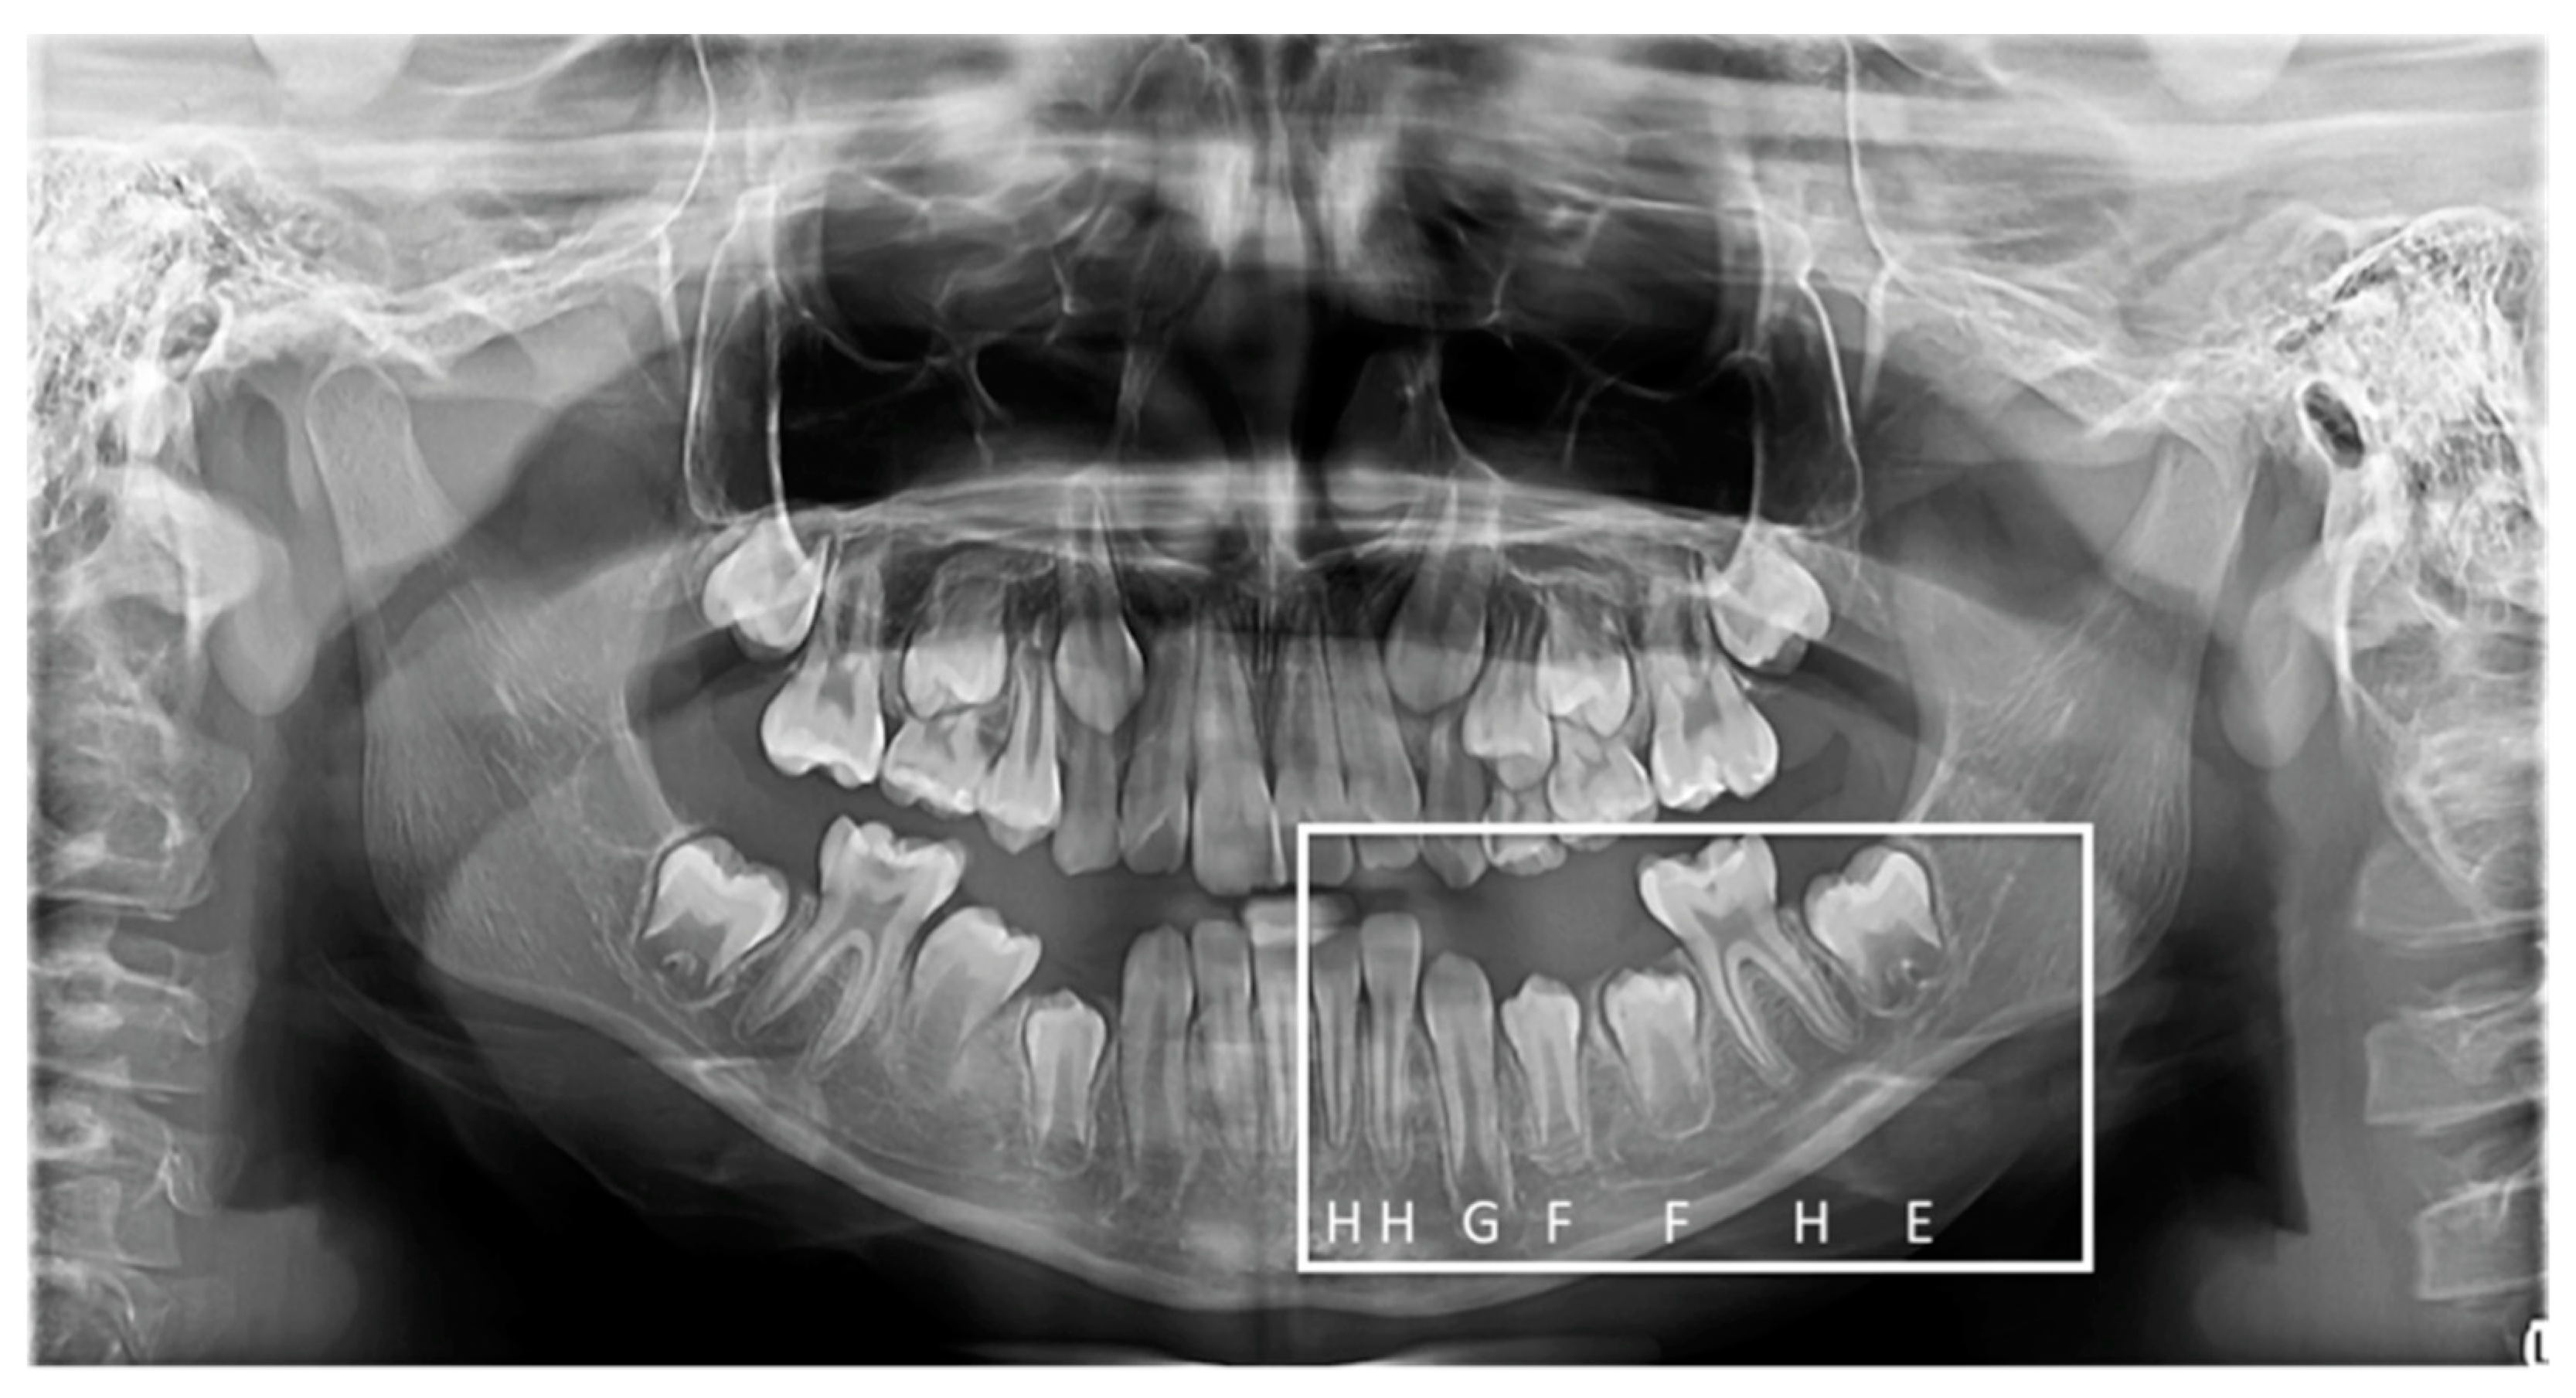

2.4. Chronological Age and Dental Age Assessment